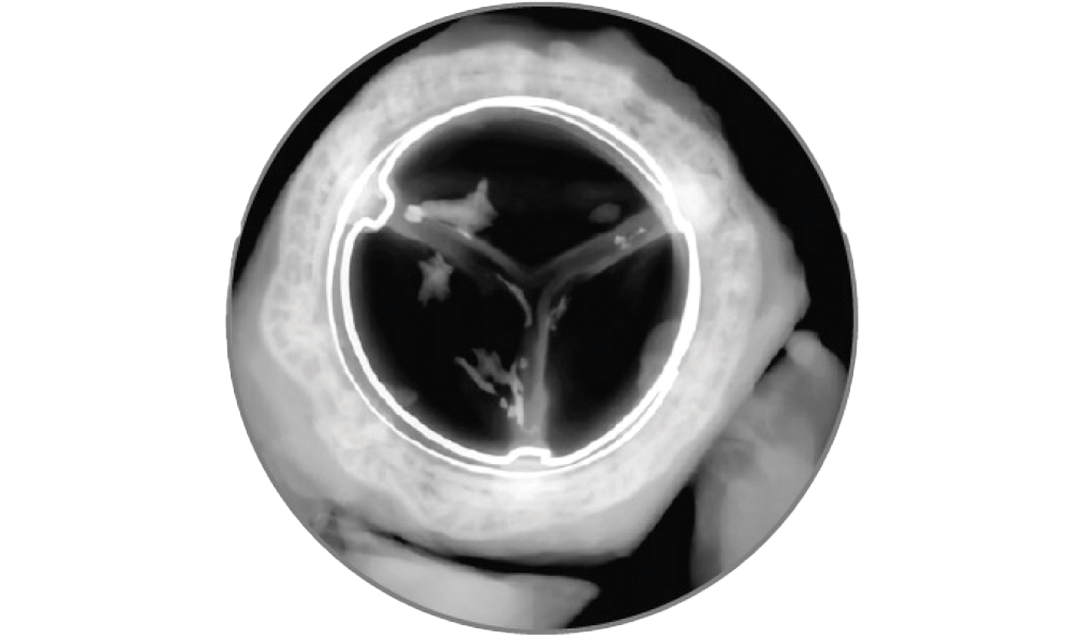

Clinically stable hemodynamics and one incident of structural valve deterioration (SVD) through 5 years.

Reduced calcification after 8 months, exceeding the 5-month reporting requirement